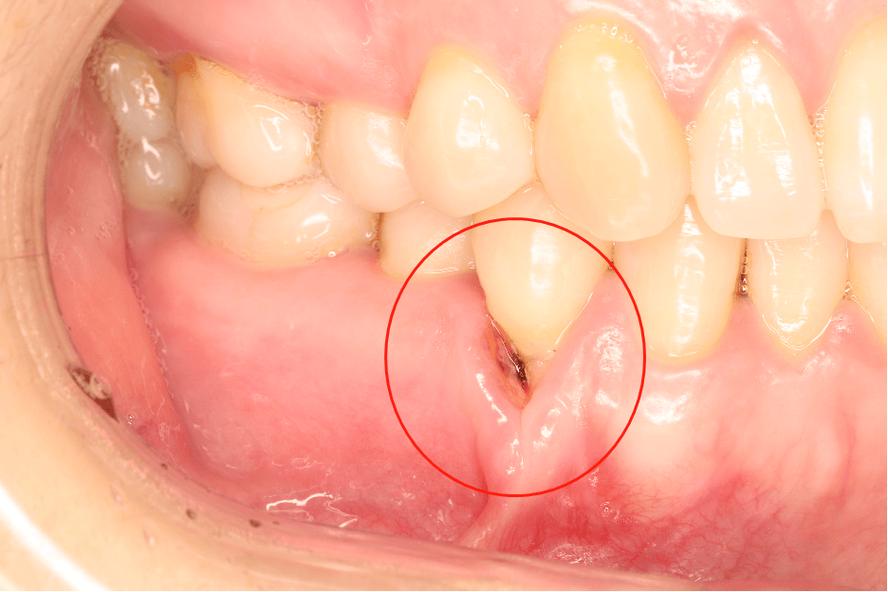

正畸后牙龈萎缩多见于前牙区,尤其是下前牙唇侧,表现为牙龈缘位置降低、牙根暴露,根据退缩程度可分为三级(见下表):

萎缩区域牙龈质地可能变薄、颜色变浅,探诊易出血,若合并牙槽骨吸收,牙齿可能出现松动度增加。